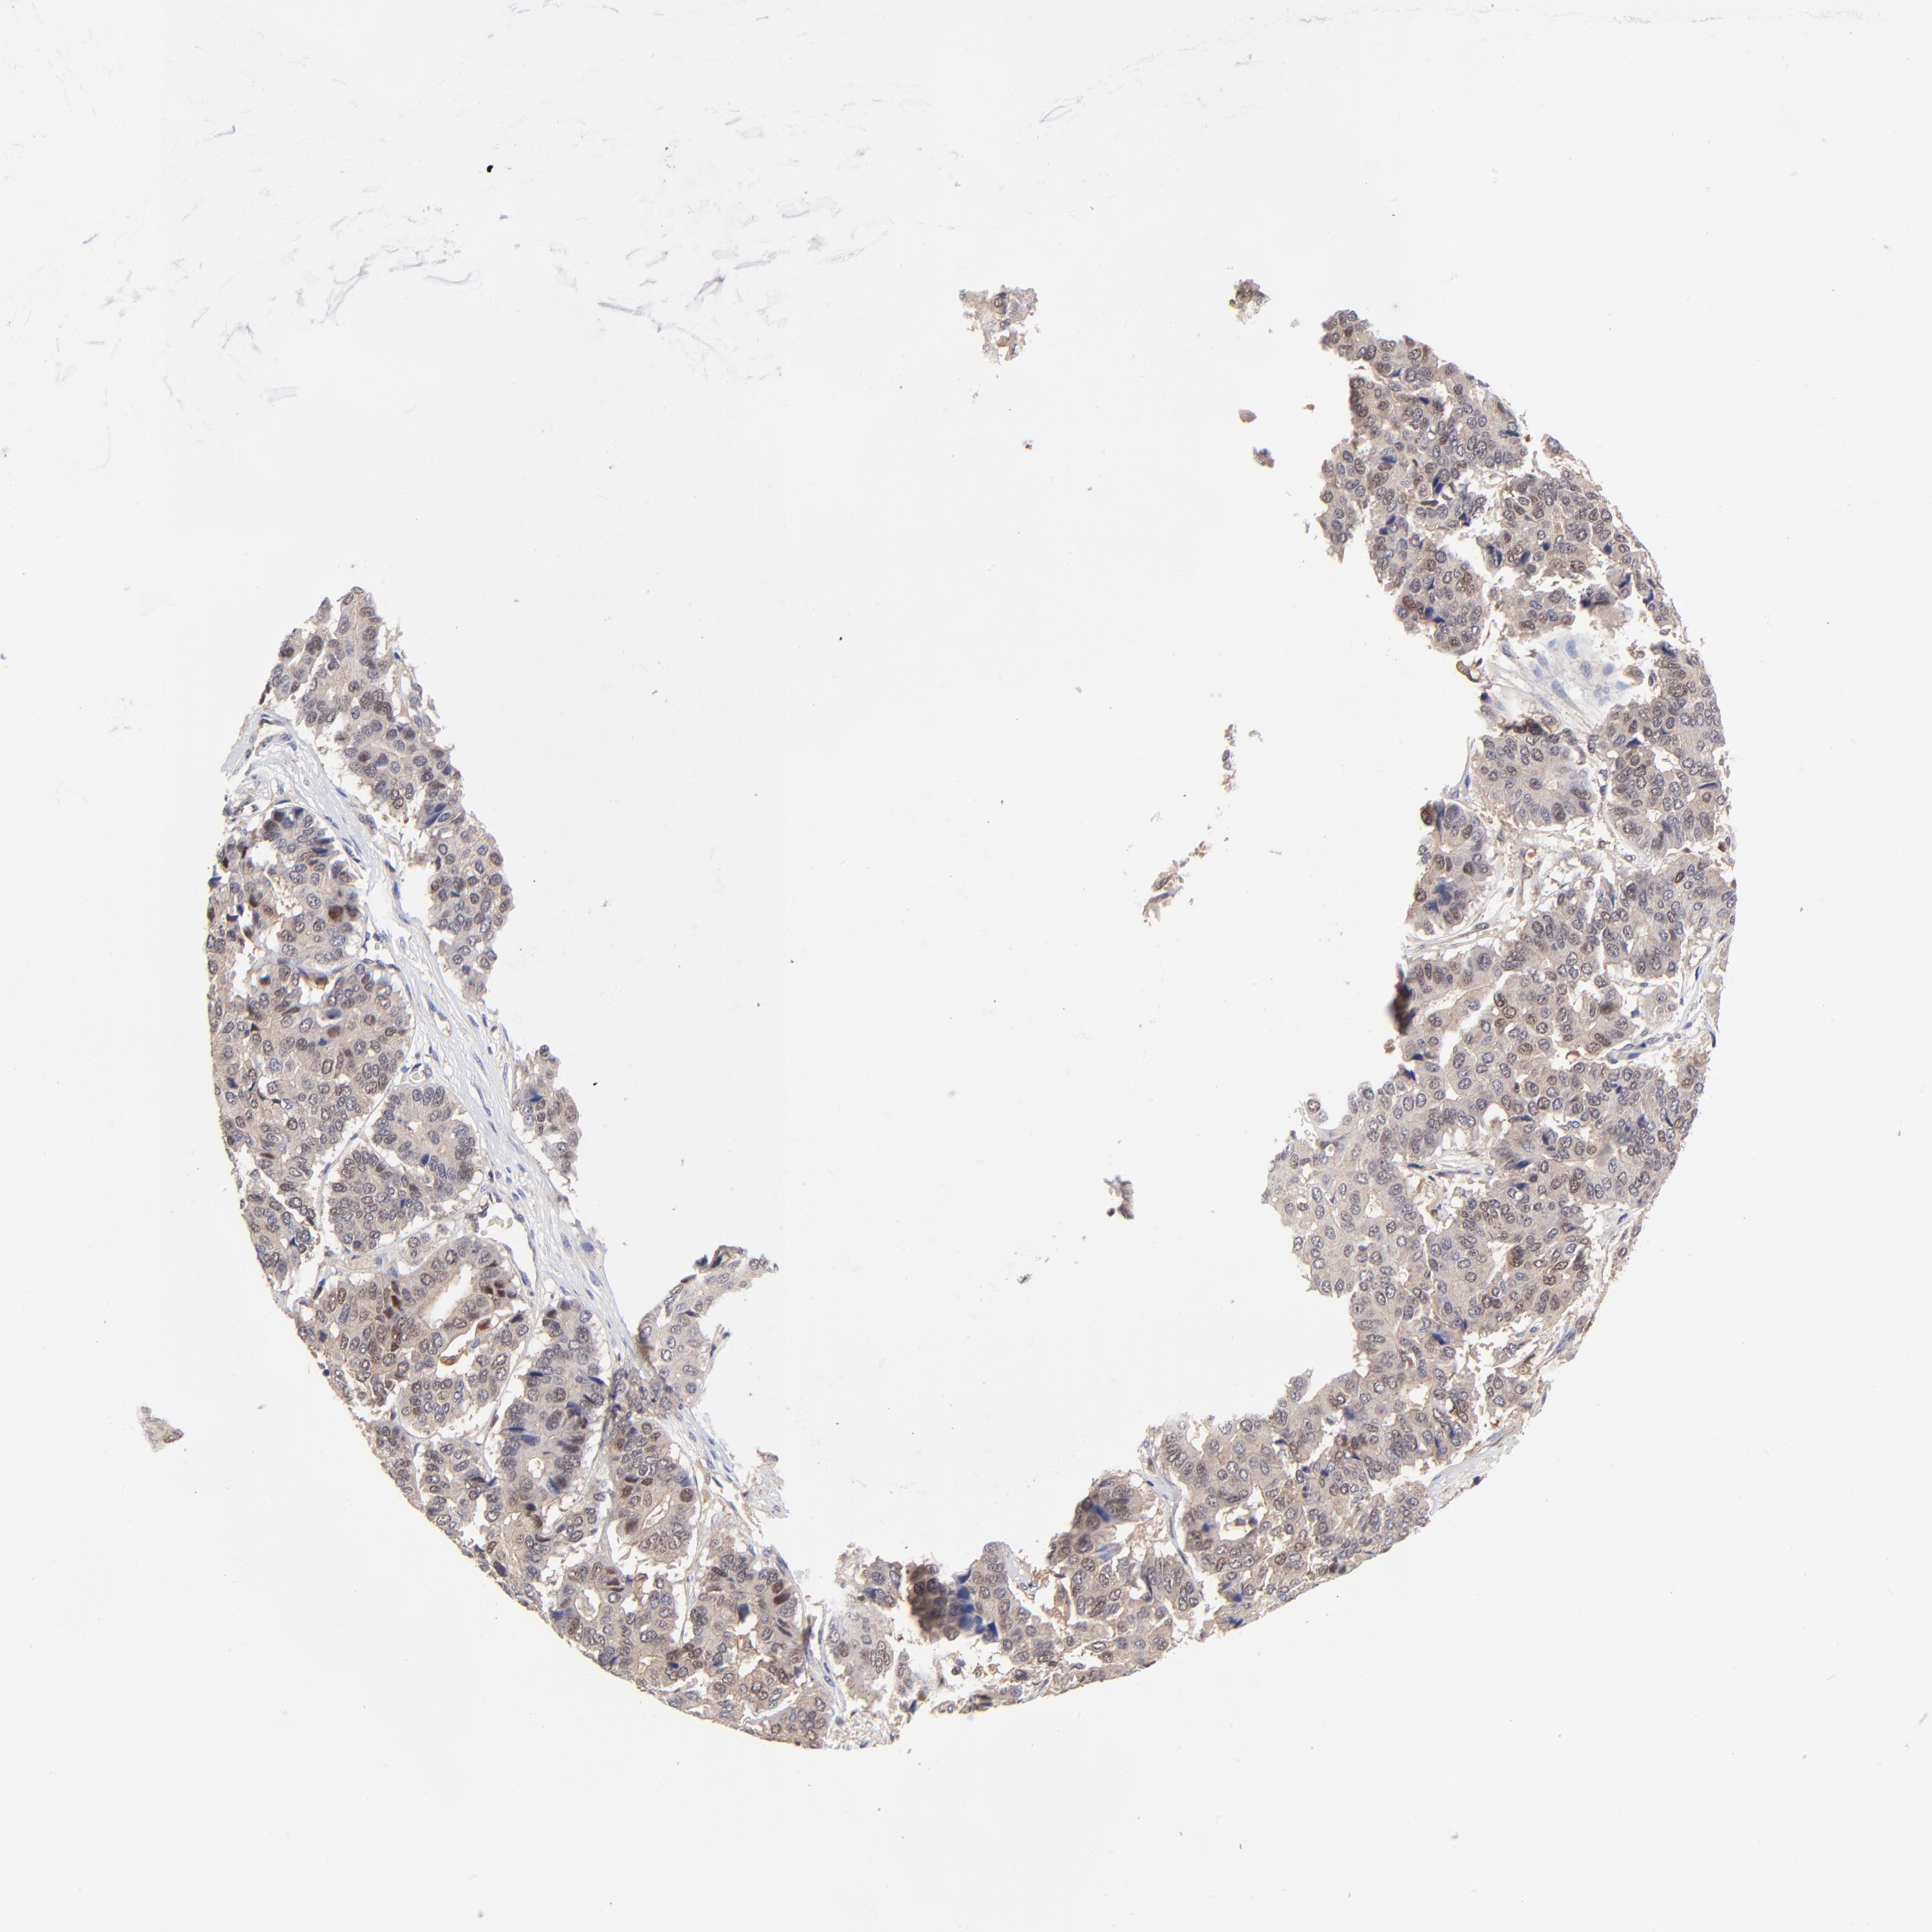

PANCREATIC CANCER - Protein expressioni

A mouse-over function shows sample information and annotation data. Click on an image to view it in a full screen mode. Samples can be filtered based on level of antibody staining by selecting one or several of the following categories: high, medium, low and not detected. The assay and annotation is described here.

Note that samples used for immunohistochemistry by the Human Protein Atlas do not correspond to samples in the TCGA dataset.

Antibody stainingi

Antibody staining in the annotated cell types in the current human tissue is reported as not detected, low, medium, or high, based on conventional immunohistochemistry profiling in selected tissues. This score is based on the combination of the staining intensity and fraction of stained cells.

Each image is clickable and will lead to virtual microscopy that enables deeper exploration of all samples and also displays staining intensity scores, fraction scores and subcellular localization as well as patient and tissue information for each sample.

Antibody HPA002832

Staining

High

Medium

Low

Not detected

Intensity

Strong

Moderate

Weak

Negative

Quantity

>75%

75%-25%

<25%

None

Location

Nuclear

Cytoplasmic/membranous

Cytoplasmic/membranous,nuclear

Adenocarcinoma, NOS

Adenocarcinoma, metastatic, NOS